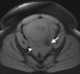

Ectopic pregnancy with hemorrhage

Ectopic pregnancy is a complication of pregnancy in which the embryo attaches outside the uterus. Signs and symptoms classically include abdominal pain and vaginal bleeding, but fewer than 50 percent of affected women have both of these symptoms. [Source: Wikipedia ]